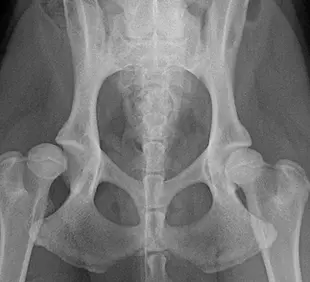

• 股関節形成不全

整形外科